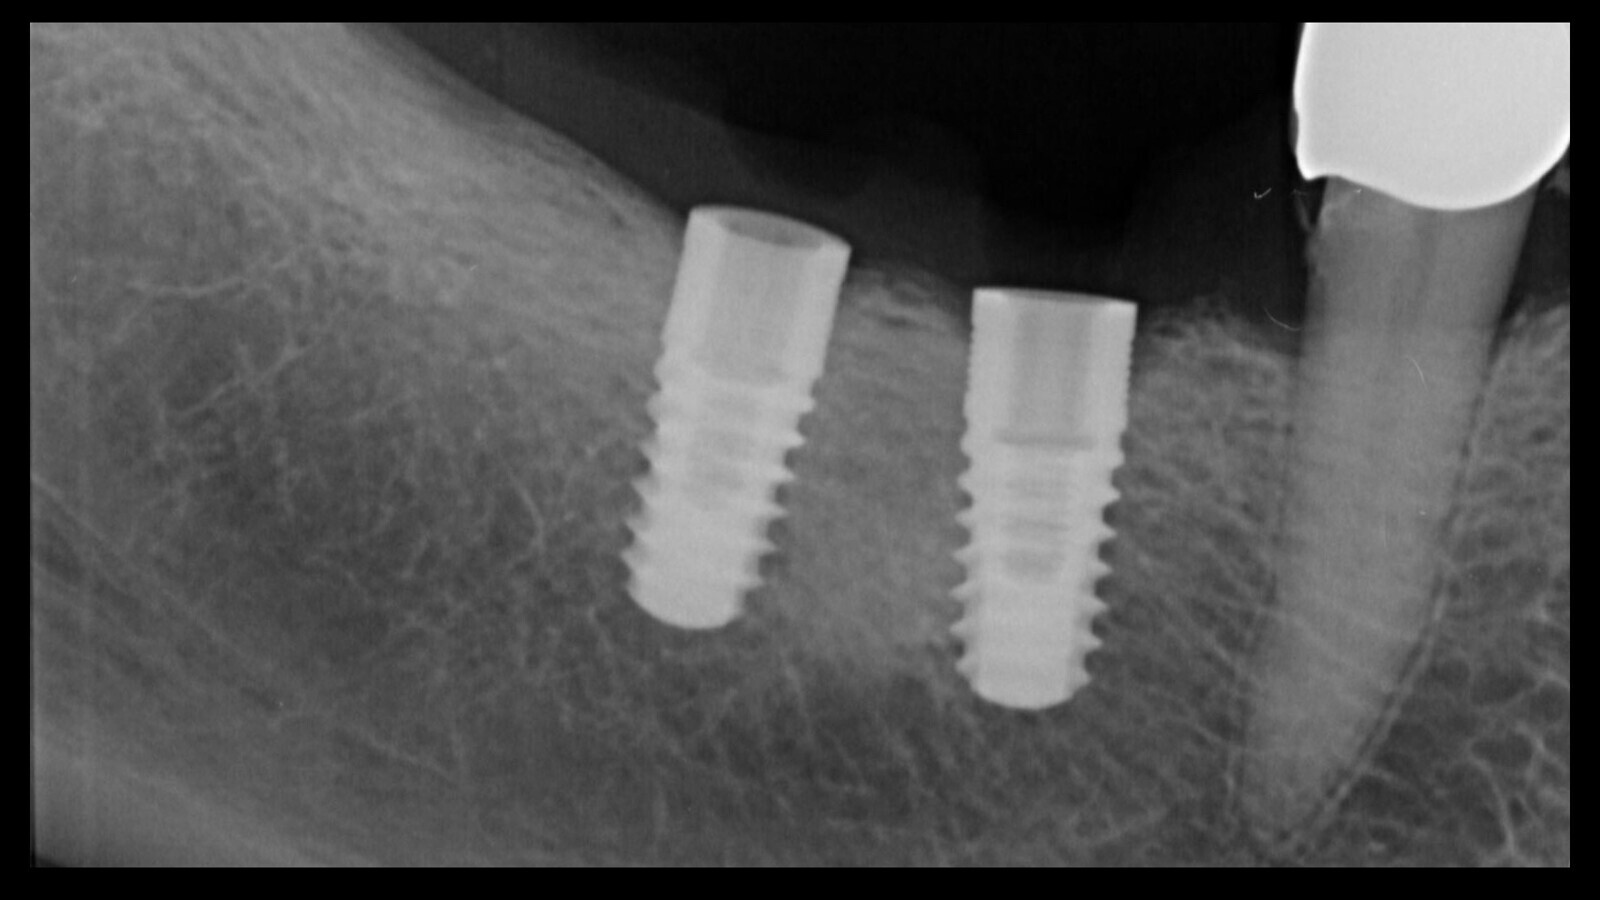

Figura 3. Esta intuición fue confirmada por el examen radiográfico, que mostró claramente el fragmento del tornillo separado dentro del implante.

Figura 11. La radiografía muestra que se realizó una remoción limpia del implante.